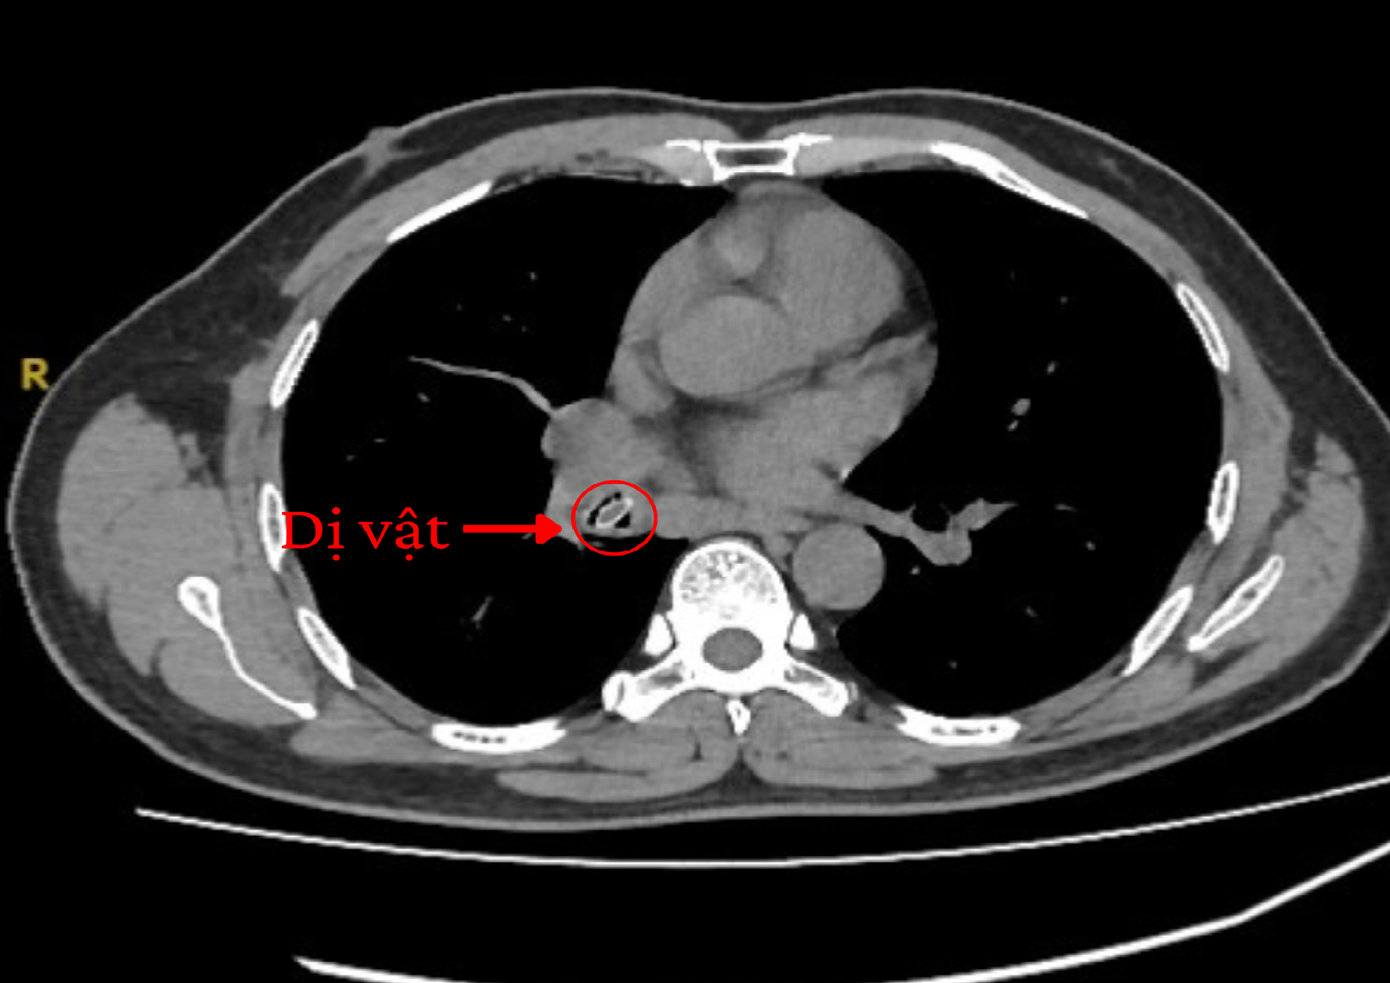

Hình ảnh kiểm tra chuyên sâu phát hiện dị vật nằm trong phổi người bệnh

Tại khoa Nội Tổng quát, kết quả chụp CT lồng ngực cho thấy một dị vật hình bầu dục, kích thước 5,5 x 7,0 x 14,5 mm nằm trong phế quản gốc bên phải, nghi là hạt trái cây. Các bác sĩ chỉ định nội soi phế quản khẩn để gắp ra, tránh biến chứng nặng.